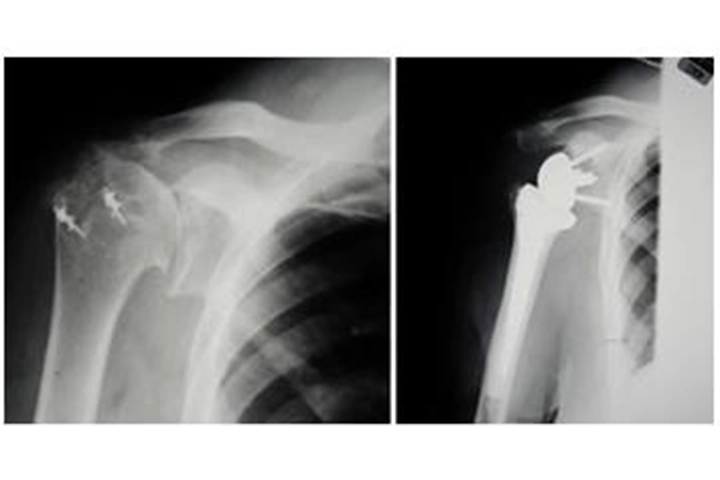

X-rays before and after reverse total shoulder replacement for cuff tear arthropathy